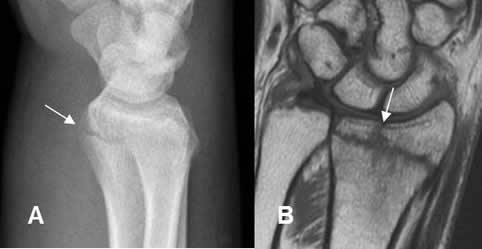

Fig 24. Fractura del escafoides.

A: Rx AP. Fractura transversa del escafoides, en su tercio medio.

B: RM sagital en T1. La fractura se identifica, como línea hipointensa.

C: RM coronal en STIR. Edema y fractura del escafoides (Flecha delgada). Adicionalmente se aprecia contusión del semilunar (Flecha gruesa).